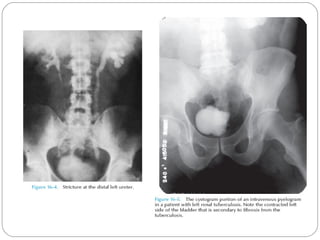

GU Tb-IVU

The most common findings being

hydrocalycosis,hydronephrosis, or hydroureter due to

stricture formation .

 Early signs include the moth-eaten appearance of

calyceal erosion and papillary irregularity- signs are

best seen on early excretory films.

Cavitary lesions communicating with the collecting

system are characteristic of TB.

 These lesions eventually enlarge as parenchymal

destruction ensues.

Fibrotic distortion of the collecting system and ureter

is also seen.

Calyceal obliteration and amputation, hydrocalycosis,

segmental or total hydronephrosis, and a shriveled

reduced capacity renal pelvis may all be signs of renal

tuberculosis

Scarring and angulation of the ureteropelvic junction

(UPJ) may also occur, the so-called “Kerr’s kink” .

Tuberculosis of the ureter is commonly seen as a rigid,

straightened “pipe-stem” ureter also beaded,

corkscrew appearance.

 Ureterovesical junction obstruction is caused by

tuberculous cystitis or strictures of the distal third of

the ureter. secondary stone formation on top of this

stricture .

The cystogram films may show a small contracted

bladder due to excessive fibrosis